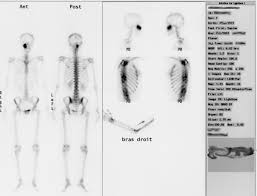

Scintigraphie

La scintigraphie est une méthode d'imagerie médicale qui procède par l'administration, dans l'organisme, d'isotopes radioactifs afin de produire une image médicale par la détection des rayonnements émis par ces isotopes après captation par les organes à examiner.

La scintigraphie est une imagerie fonctionnelle, c’est-à-dire du fonctionnement.

La scintigraphie est une imagerie d'émission (c’est-à-dire que le rayonnement vient du patient après injection du traceur) par opposition à l'imagerie conventionnelle radiologique qui est une imagerie de transmission (le faisceau est externe et traverse le patient).

On injecte au patient un traceur : c'est l'association d'une molécule vectrice et d'un marqueur radioactif.